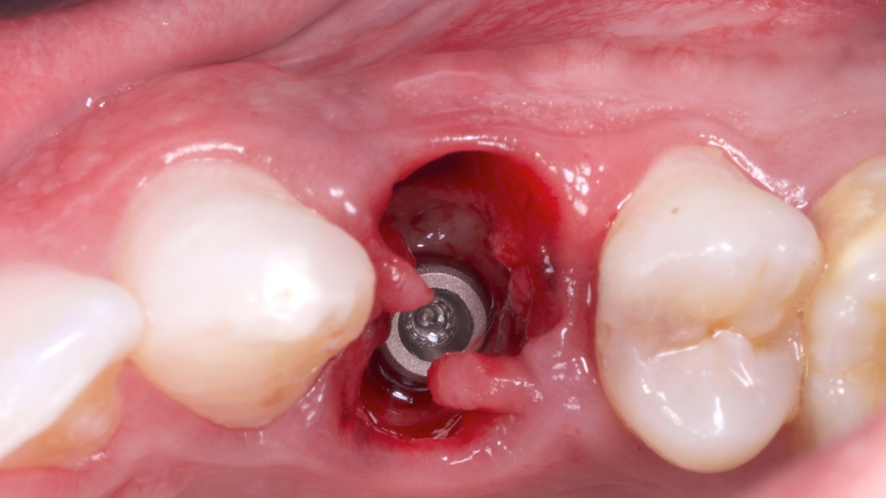

Após a exodontia foi posicionado o guia cirúrgico impresso e iniciou-se o protocolo de fresagem do kit cirúrgico Implaguide da Implacil De Bortoli: fresa lança 2,0, seguida pela fresa 3,5×13, buscando subfresagem para maior estabilidade primária. O implante dentário instalado foi o Maestro de 4x13mm (Implacil De Bortoli). Foi realizado em seguida a instalação do pilar Ideale 4,5 x 4 x 2,5 mm e a coifa parafusada do pilar Ideale 4,5x4mm.

O GAP vestibular foi preenchido com enxerto ósseo heterógeno com matriz colágeno Extra Graft (Implacil De Bortoli), o qual foi colocado e compactado.

Em seguida foi realizado a captura do provisório em PMMA na coifa de titânio com resina fluida e após acréscimos, acabamento e polimento fora da boca, o provisório foi aparafusado e a cirurgia foi finalizada sem a necessidade de sutura.